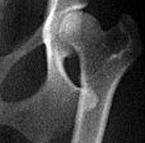

Дисплазия тазобедренного сустава у собак — это генетически унаследованное заболевание опорно-двигательного аппарата. У здоровых собак тазобедренный сустав плотно и плавно прилегает друг к другу. Однако у собак с дисплазией тазобедренного сустава головка бедра свободно входит в таз, вызывая чрезмерное трение. В конце концов, хрящ, смягчающий сустав, изнашивается из-за этого смещения, и собака испытывает боль и связанную с ней хромоту. В тяжелых случаях дисплазия тазобедренного сустава может привести к полной потере подвижности задних конечностей.

Ветеринар диагностирует дисплазию тазобедренного сустава с помощью внешнего осмотра (ощущение слабости в бедрах), а также рентгеновских снимков или рентгенограмм, чтобы определить степень дегенерации сустава. Легкая дисплазия тазобедренного сустава похожа на остеоартрит у людей, и собаки могут легко научиться жить с этим заболеванием и жить полной и счастливой жизнью.